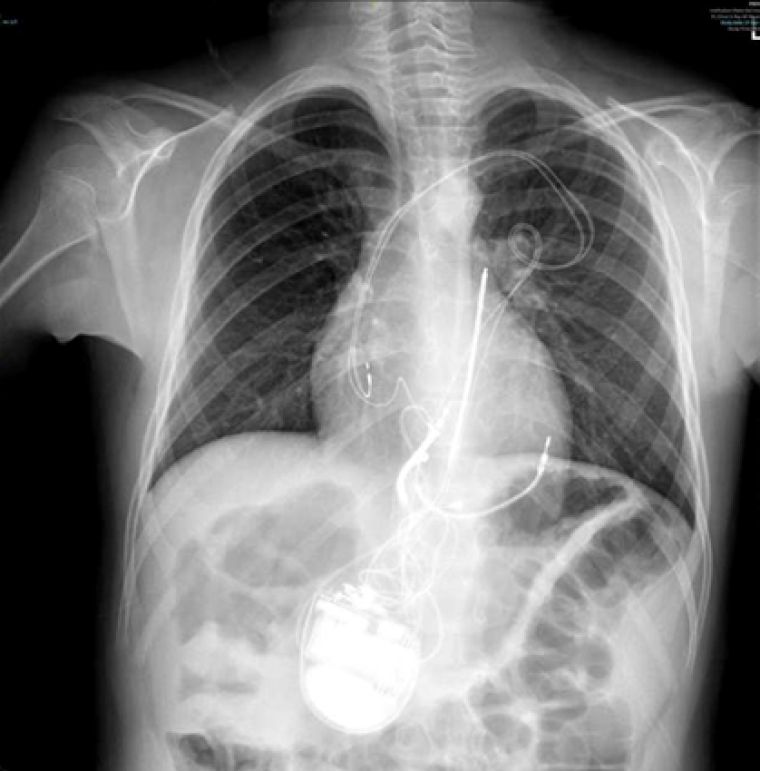

During follow up, a second episode occurred at 1.5 years of age when the infant was upset. As he was crying, his father picked him up and he started developing jerking movements of the body and developed cyanotic lips. He became limp and unresponsive, at which point his parents gave some rescue breaths and he recovered. This episode lasted a total of roughly two minutes. The local hospital referred the case to our unit for consultation regarding ongoing management, given the patient’s ongoing episodes, despite treatment on propranolol and having reached a QTc of 600ms (image 2). Given the presence of abnormal QT prolongation and suspected arrhythmogenic in nature episodes, a consensus was reached for the implantation of an implantable cardioverter-defibrillator (ICD) and subsequently an epicardial, single-chamber device was successfully fitted in our unit. The patient was discharged home on mexiletine (5mg/kg/day) and propranolol (1.75mg/kg/day).

During the procedure, VF was induced with burst pacing after administering Isoprenaline. Despite adjusting the sensing threshold to 0.6mV, the ICD could not effectively detect VF, and a successful shock required changing the configuration from coil to can. Recognizing the device's inability to safely provide effective therapy during VF, a multi-disciplinary team meeting approved a "hybrid approach". The patient underwent ICD system revision, with the generator changed and left in an abdominal position. A transvenous atrial and ventricular pace-sense lead was inserted and tunnelled subcutaneously to the abdominal pocket, and an ICD shock coil was positioned subcutaneously anteriorly at the left parasternal site, with the shock set between the prior epicardial coil and the new subcutaneous coil (Image 3, 4a,b).